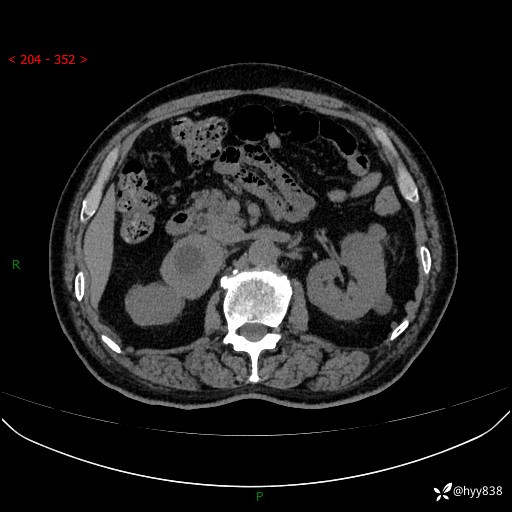

【患者信息】:76岁/男

【主诉】:检查发现右侧肾上腺占位6天

【现病史及既往史】:患者6天前体检发现右侧肾上腺占位,无腰痛,无放射痛,无尿频、尿急、尿痛及肉眼血尿,无畏寒、发热,无恶心、呕吐,今为求进一步治疗,遂来我院就诊,门诊拟“右侧肾上腺占位”收住入院。 起病以来,患者精神、饮食、睡眠可,大小便如常,体力体重无明显变化。

【检查】:肾上腺CT平扫+增强